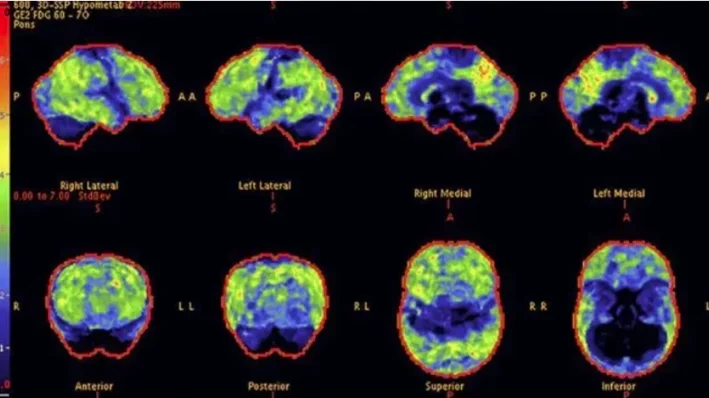

Above: PET scans show reduced brain activity in a 68-year-old woman with progressive symptoms of memory loss. The stained areas indicate low levels of acetylcholine, associated with the accumulation of invisible brain toxins.

Above: After 8 weeks with Memory Lift, PET scans show a significant improvement in brain activity - especially in the areas linked to memory retention and focus. The natural production of acetylcholine has been restored, resulting in greater clarity and cognition.